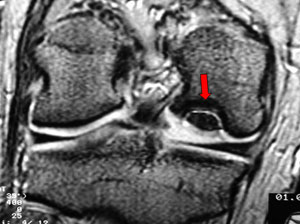

Deslocamento Patelar + Lesão do Retináculo

![]() |